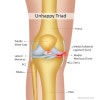

ACL injury 단독 손상은 10~20% 이하로 동반 손상이 일어나는 빈도는 매우 높습니다.

약 80%에서 골좌상이 동반되고, 절반 이상의 환자에서 유의한 관절 연골 손상, 약 5~20%의 환자에서 측부인대 손상이 동반되는 등 다양한 동반 손상이 빈번하게 발생할 수 있습니다.

전통적으로 불행 삼증후(unhappy triad)가 알려져 왔으나, 실제로는 ACL injury시 lateral meniscus injury가 더 흔합니다.

적절한 치료가 되지 않은 만성 전방십자인대 손상에서는 내측 반월상 연골 손상이 증가하게 됩니다.